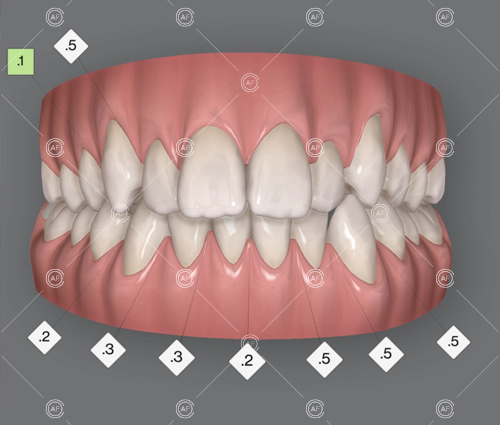

The aim of the treatment was to relieve upper and lower arch crowding, correct lower centre line shift, treat class 1 incisors and buccal segments.

MH debonded in December 2020, with overall treatment time of around 14 months.

She was provided with upper and lower vacuum form retainers, and asked to wear these every night for the first year, and alternate nights for the second year onwards, indefinitely for as long as she wanted her teeth to remain straight. High quality finish was maintained at one year post-debond.